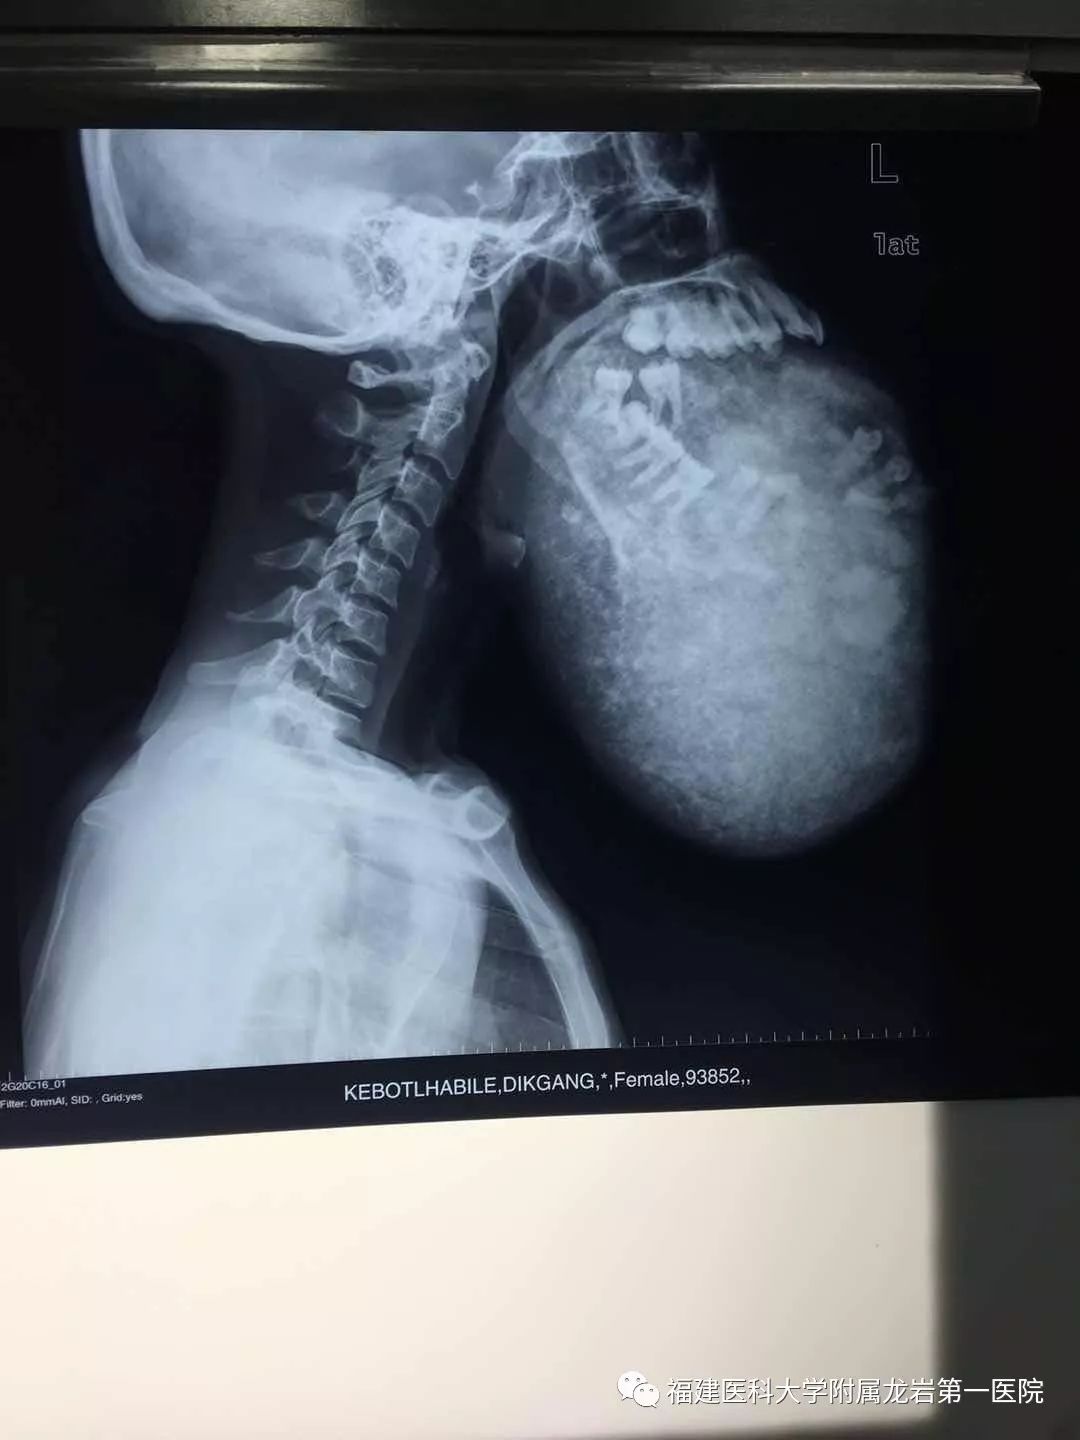

近日,公主玛丽娜医院收治了一名骨瘦如柴、下颌骨巨大肿物的妇女。据了解,该妇女的下颌骨肿物在短时间迅速生长,并逐渐压迫食道、气管,从而影响进食、呼吸,甚至严重危胁生命。中国援非医疗队陈希杭医生接诊后,与王棕皆医生认真研讨病例,确定手术摘除肿瘤是挽救患者生命的选择,然而 ,由于肿瘤紧邻颈动脉,而且与临近的静脉、神经紧密粘连,术中极易出现大出血、脑血栓、偏瘫、甚至死亡,具有极大的风险。但为了挽救患者的生命,必须尽快手术,为患者博取一线生机。

经过术前周密的准备,王棕皆医生为患者进行全身麻醉,并密切监视患者的生命体征,手术主刀医生为患者谨慎操作,避免损伤肿瘤周围的丰富神经及动、静脉血管,终于将重达2.8公斤的硕大肿瘤完整切除,手术十分顺利。